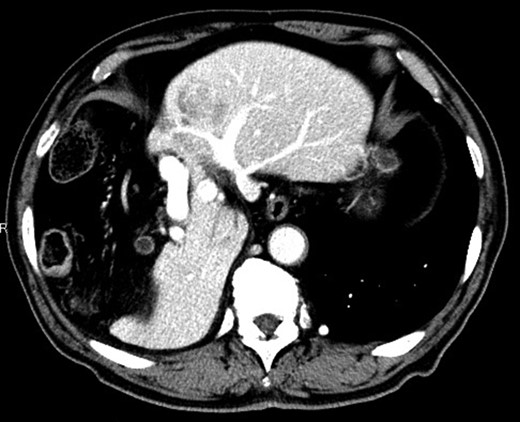

An 80-year-old man was undergoing follow-up because he had undergone surgery for thyroid cancer 2 years previously in the Department of Head and Neck Surgery at our hospital. Dynamic contrast-enhanced computed tomography (CT) during follow-up for thyroid cancer revealed a mass measuring 40 mm in diameter with high attenuation, early-phase enhancement, washout during the late-phase in S3 and hypoplasia of the right hepatic lobe with the Chilaiditi sign, which is a segmental interposition of the colon between the liver and the diaphragm (Fig. 1). Our preoperative diagnosis was HCC, and the clinical stage was T1bN0M0, or Stage IB, in terms of the Union for International Cancer Control classification (eighth edition).

Dynamic contrast-enhanced CT showing a 40-mm nodule in S3 and hypoplasia of the right hepatic lobe with the Chilaiditi sign.